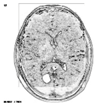

This work collects images from the Kaggle Brain MRI for Brain Tumor Detection dataset, which consists of 253 files with cancer and non-cancer brain images. The sample MRI is illustrated in Figure 2. The dataset has two folders: no tumor encoded as 0 and tumor as 1. The labeled data is more helpful in extracting the patterns from the MRI, which is used to predict the new images related output. The collected image consists of noise information that reduces the performance of brain tumor recognition accuracy. Therefore, image noise should be eliminated to improve the overall prediction efficiency.

Figure 2.

MRI samples Normal Brain MRI (Y1 to Y8) Benign tumor MRI (Y9 to Y15) Malignant tumor MRI (Y16 to Y21).